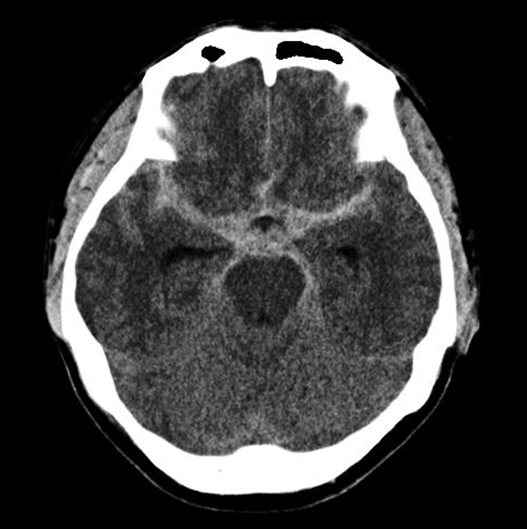

수술전 뇌CT 영상에서 뇌지주막하출혈 소견이 보임

CT 혈관조영술상 뇌동맥류 발견

뇌혈관조영술로 동맥류에 대해 정밀검사

혈관내 코일색전술을 통해 개두술 없이 동맥류를 치료함